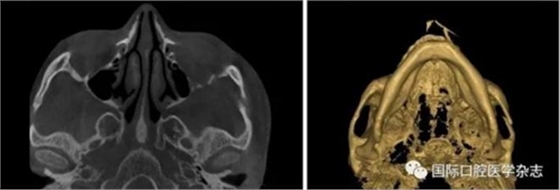

3.3 口腔頜面部損傷、腫瘤

頜面部上下頜骨、顴骨及顴弓骨折、骨折片移位壓迫咀嚼肌群和下頜骨喙突,影響下頜骨的活動(dòng),一般采取手術(shù)治療復(fù)位骨折斷端,恢復(fù)下頜正常運(yùn)動(dòng)。頜面部腫瘤侵犯咀嚼肌群引起張口受限,一般行手術(shù)治療切除病灶(圖20)。

A:術(shù)前開口度;B:術(shù)后開口度;C:術(shù)前影像學(xué)檢查片;D:術(shù)后影像學(xué)檢查片。

圖 19 關(guān)節(jié)成形術(shù)前后對(duì)比

圖 20 顴弓骨折修復(fù)術(shù)前后對(duì)比